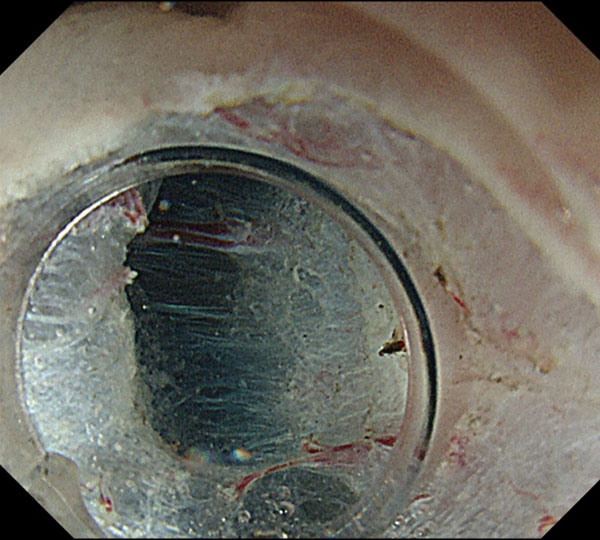

6. 一旦、ポケットからでて、剥離がどの程度進んだか確認しています。

7. 十分に剥離したのち、残った粘膜を切開し切除が終了しました。